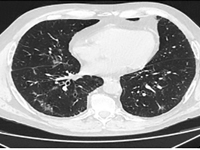

Internal MedicineLung cancer accounts for the largest number of cancer deaths worldwide [1]. Despite advances in treatment, incidence and mortality rates continue to rise. A 2018 GLOBOCAN analysis reported 2.09 million new cases of lung cancer and 1.76 million deaths from lung cancer worldwide [2]. There are two main histological types: small cell lung cancer (DRP) and non-small cell lung cancer (NDRP). NDRP accounts for about 85% of all lung cancer cases. It includes various subtypes such as adenocarcinoma, squamous cell carcinoma and large cell carcinoma. The most common subtype is adenocarcinoma accounting for 45% of NDRP cases. The most important risk factor for developing lung cancer is smoking, especially among the male population. The use of filtered cigarettes, which reduce the amount of tar entering the lungs, correlates with an increase in the incidence of lung adenocarcinoma, which is associated with stronger inhalation of carcinogens into the fine airways. Other compounds that may have an effect on cancer development are asbestos, radon, nickel, cadmium, chromium, silica and arsenic. The development of molecular studies at the beginning of the 20th century made it possible to identify the genetic basis of the disease by demonstrating the presence of mutations or rearrangements of TP53, MYC, BCL2 genes in small cell carcinoma and EGFR, KRAS, MET, BRAF, NTRK, ROS1, ALK, RET, PIK3CA genes in non-small cell carcinoma [3]. The percentage of non-squamous NDRP patients with mutations in the gene for the epidermal growth factor receptor (EGFR) is 10-15 (in Caucasian patients) to more than 40% (in Asian patients) [4]. A deletion in exon 19 and a substitution at codon 858 (L858R) in exon 21 account for 80-90% of mutations within the tyrosine kinase coding domain of the EGFR gene [4]. Lung cancer manifests as cough, hemoptysis, chest pain, shortness of breath and/or hoarseness. In the case of adenocarcinoma, brain metastases manifesting as headache, vomiting, visual field disturbances, seizures or neurological deficits are common. After appropriate laboratory and imaging tests and histopathological evaluation, it is possible to assess the histological type and stage of the cancer. Depending on the patient's general condition, tumor stage and concomitant diseases, different treatment methods are used. For low-grade cancer (stages I, II and IIIA), surgery is used, often in combination with chemotherapy and radiation therapy. For stage IIIB patients, the therapy of choice is chemoradiotherapy, and if chemoradiotherapy is not available, the treatment is the same as for patients with generalized NDRP. Therapy for patients with distant metastases (stage IV) is aimed at reducing the discomfort and symptoms of progressive disease and prolonging life. For this purpose, chemotherapy, immunotherapy or molecularly targeted therapy are used [5]. Molecularly targeted therapy for lung cancer with EGFR gene mutations is made possible by the use of tyrosine kinase inhibitors (IKTs). IKTs inhibit intracellular phosphorylation of EGFR which leads to the arrest of cell differentiation, proliferation and angiogenesis. EGFR IKTs are divided into three generations. Erlotinib and gefitinib are the first-generation reversible IKTs. They are effective in the presence of the most common mutations in exon 19 and 21. Second-generation irreversible IKTs, which include afatinib and dacomitinib, show a broader spectrum of action. They block the transmission of signals formed by ErbB1 (EGFR), ErbB2 (HER2), ErbB3 and ErbB4 receptors, and can be effective in the presence of rare mutations in exons 18, 19, 20 and 21. It is possible to acquire resistance to first- and second-generation IKTs. Ozymertinib, an irreversible third-generation IKT, by acting on cells with the T790M mutation in exon 20 of the EGFR gene, overcomes resistance to treatment with older-generation EGFR IKTs, but can also be used in 1st-line treatment in NDRP patients regardless of the type of mutation in exons 18-21 of the EGFR gene [6]. The global COVID-19 pandemic poses a therapeutic challenge to healthcare, especially among oncology patients. A retrospective analysis from Wuhan showed that the risk of COVID-19 infection was 2.31 times higher among cancer patients than in healthy individuals. Smoking, age, male gender, cancer status, poor performance status (≥2 on the ECOG scale) and treatment with hydroxychloroquine with azithromycin were risk factors for increased 30-day mortality among COVID-19 patients [7]. Hospital visits during the pandemic and the use of immunosuppressive medications are major contributors to COVID-19 infection in lung cancer patients [8]. A study conducted in China, showed that NDRP patients over 60 years of age are particularly vulnerable to COVID-19 infection and a more severe course of the disease. Many respiratory symptoms in COVID-19 i.e. shortness of breath, cough, fever overlap with those of lung cancer. This creates a difficulty in differential diagnosis between the two disease entities. The diagnosis of COVID-19 is usually made on the basis of clinical history and PCR test and/or antigen test in a sample from nasopharyngeal secretions. Recognition of typical lesions seen on chest CT scan is also helpful. Multifocal opacities of the frosted-glass type with predilection for the lower lobes are present in 75% of patients [9]. A study conducted in New York among lung cancer patients with concurrent SARS-CoV2 infection showed the need for hospitalization in 62% of patients, 21% of whom required ICU hospitalization. Of the 102 patients participating in the study, 25% died. Survival was more dependent on the comorbidity of COPD (chronic obstructive pulmonary disease) and smoking than on tumor histology or PD-L1 (programmed death ligand 1) expression on tumor cells [10].